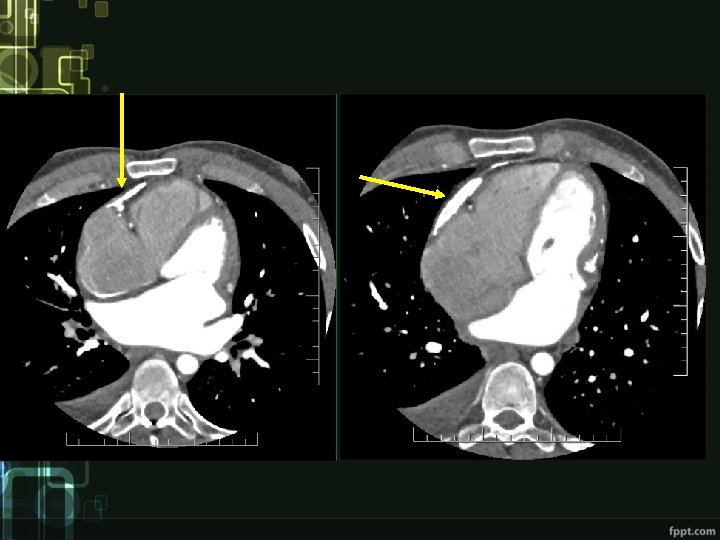

cardiac tamponade

Diagnostics • Clinical picture • ECG – low voltage, repolarization changes (inverted T waves) • ECHO – thickened pericardium, impaired ventricular filling, „dancing septum“, IVC and atrial dilatation • Other imaging techniques